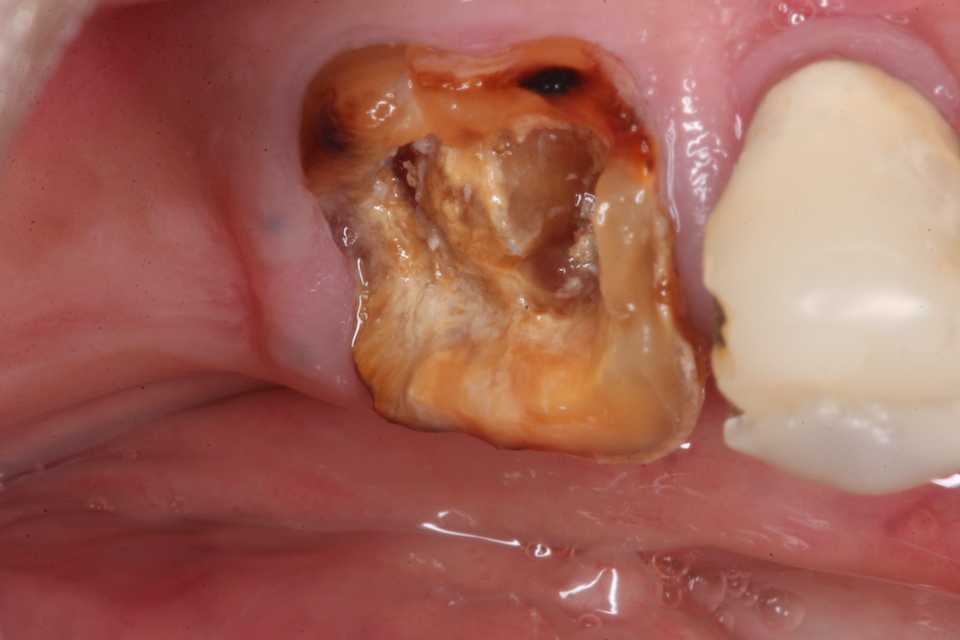

11歳女子、左上6、頬側カリエス、時々沁みるこの部分の虫歯は頬の粘膜に覆われているので、酸素不足になり酸素濃度差腐食が起こりやすい。歯にも電気(水素イオン:プロトン)が流れ、金属と同じような腐食が起こる。これが虫歯ということになる。それ以前にこの歯が萌えたての頃、虫歯になりやすい環境があったのだろう。白や黒に着色した帯が見える。これは初期のエナメル質の虫歯、脱灰と言われる現象。元々弱いここから先程の酸素濃度差腐食が起こるということ。画像が撮りにくかったので、見苦しくて申し訳ありません。では時系列でどうぞ角の部分に穴が開いている。実像:少し虫歯を削ると向こう側がチラッと見える。3MIX+α-TCP実像:CR充填後鏡像